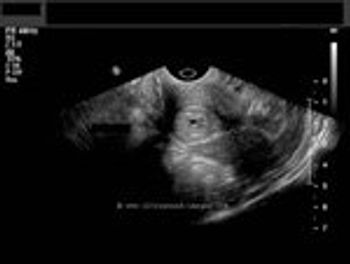

This is a 30 year old female with polymenorrhea with dysmenorrhoea. What do the ultrasound images show?